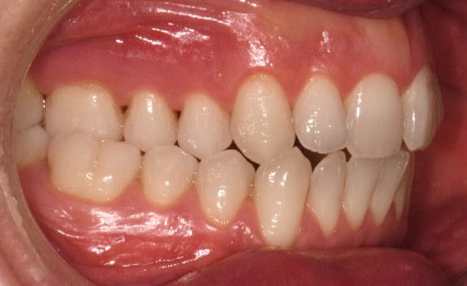

A 38-year-old male patient sought orthodontic treatment with both functional and esthetic concerns. His main complaints included the appearance of an inverted smile arc, reduced incisor display, and a general lack of harmony in his smile.

The extraoral examination revealed a long facial type with an increased lower facial third, nasolabial folds accentuated by insufficient midface support, and broad buccal corridors due to maxillary compression. Intraoral analysis showed a posterior crossbite, negative torque on posterior teeth, and an altered occlusal balance. Radiographic and cephalometric evaluation confirmed the clinical findings, with an increased mandibularplane angle and mandibular posterior rotation. This rotation contributed to a convexity of +4 mm, although the underlying problem was a retruded maxilla with insufficient midface support. Vertical facial height was also increased. Importantly, the temporomandibular joint evaluation showed a posterior condylar position with intact cortical bone, no pain, and no joint sounds.

(Images: Intraoral Initial)